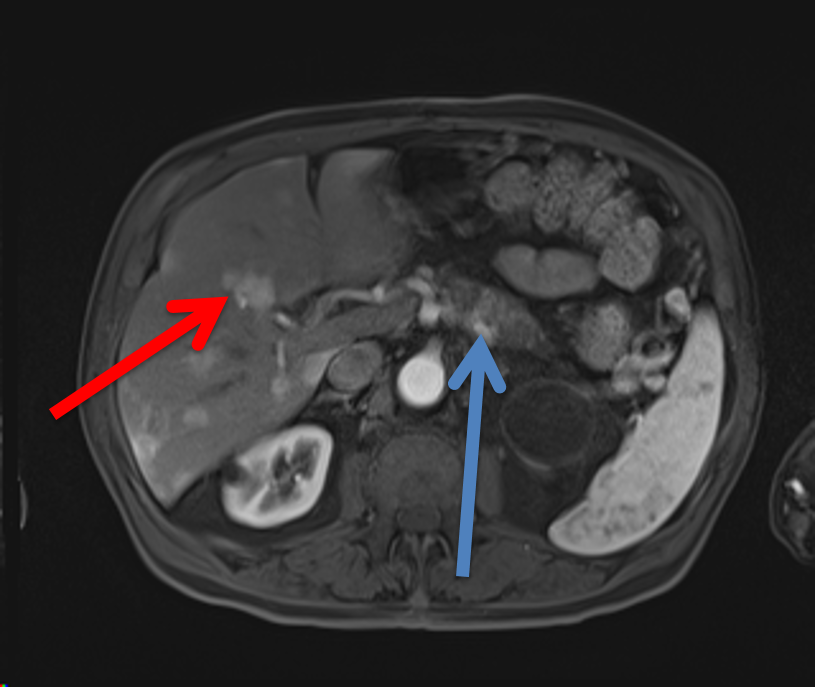

MRCP Sequences

- MRCP sequences are heavily T2 weighted.

- T2 weighted images have long TR times, and T1 weighted images have short TR times.

- Long TE times allow for tissues to lose transverse magnetization. Water maintains its transverse magnetization, allowing for images of the fluid-filled biliary tree.